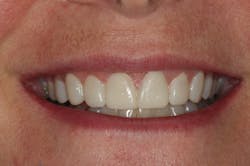

In this situation, we were able to achieve all of our functional and esthetics goals, which resulted in a happy patient (figures 22 and 23). The soft-tissue architecture was revised. The incisal edge positions and proportions were corrected. The shade, as well as the micro- and macro-esthetics, was improved. The exposed dentin and pulps of teeth Nos. 7–10 were covered and protected. Most importantly, we fulfilled the 5 requirements of occlusal stability for long-term functional success (figures 24 and 25).